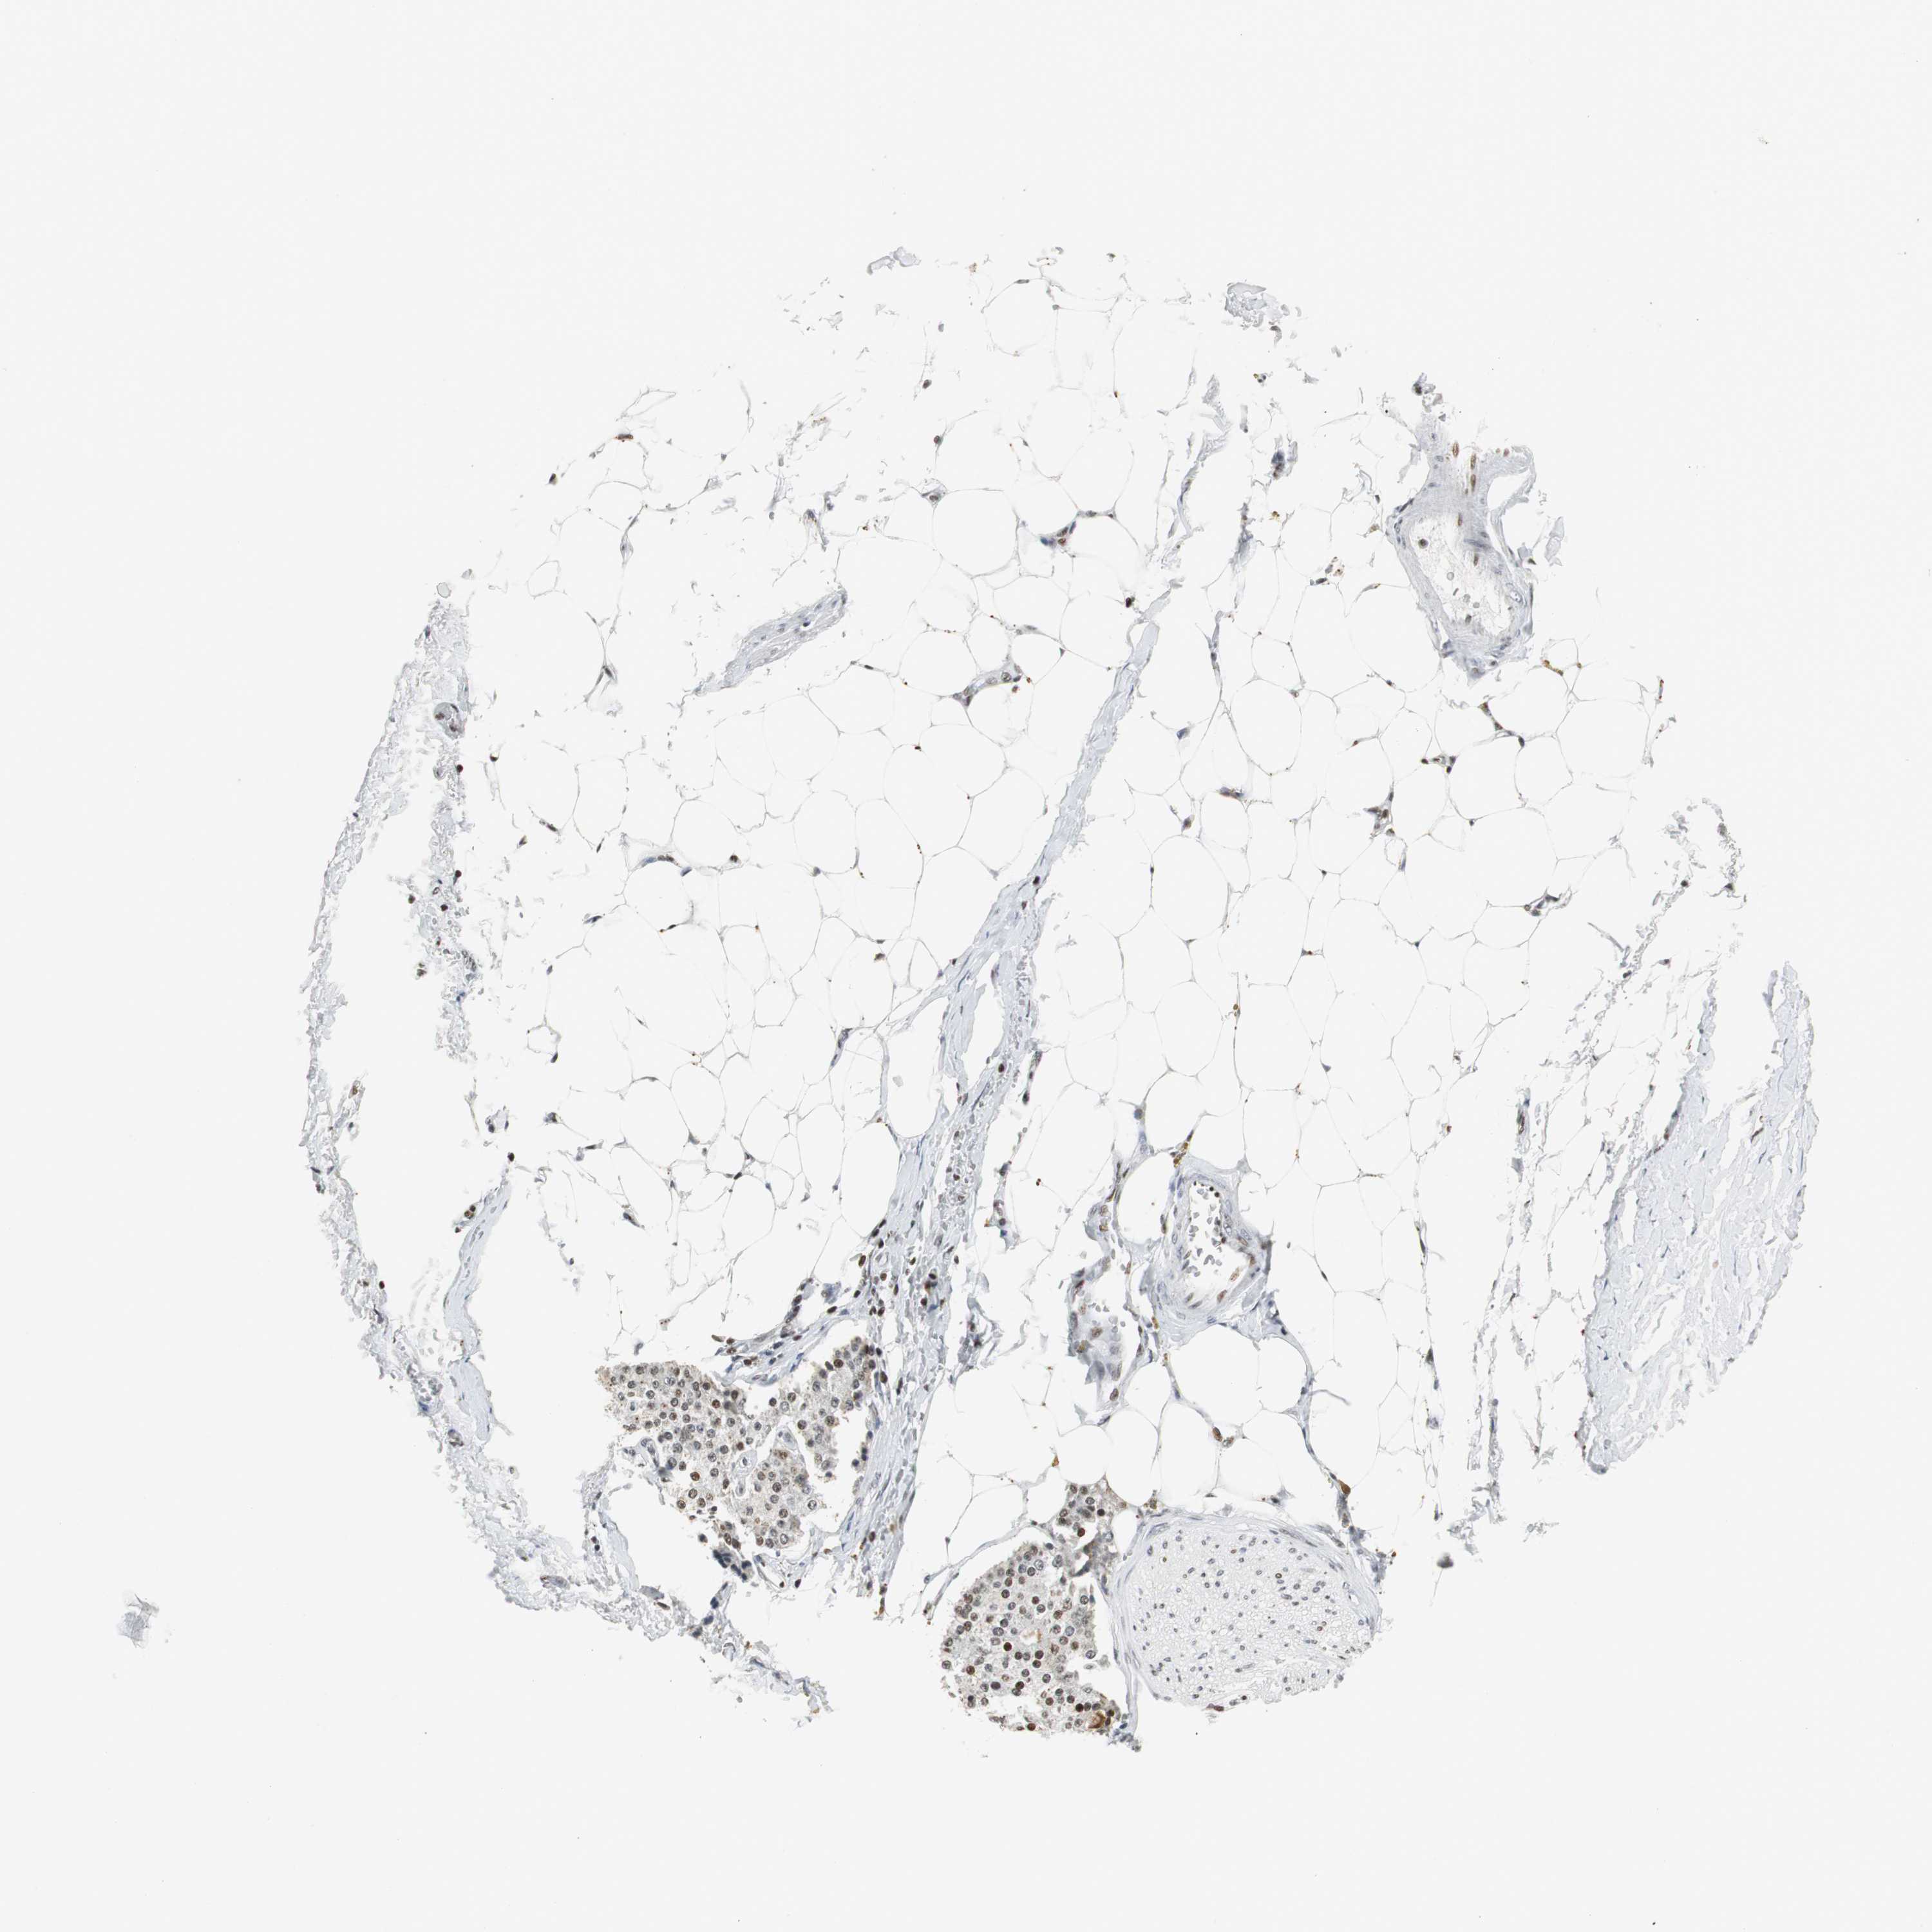

RBBP4